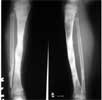

This is the case of R.P., a two year old boy who at age one year had osteomyelitis of the left tibia. He underwent debridement and the leg was protected with a cast for a total of eight months. After removal of the plaster it was noted that he had a progressive deformity of the leg. The patient subsequently consulted at the Pediatric Orthopaedic Section and Ilizarov and Limb Deformity Service of the Department of Orthopaedics, Philippine General Hospital.

On physical examination, R.P. has a marked anterolateral bowing of the right leg. There was also shortening of the leg. No draining sinus was present and the limb has intact neurovascular status.

R.P. underwent application of Ilizarov Circular Fixator. The pseudoarthrosis site was not surgically explored. The aim of the fixation was to provide bone fragment stability in order to promote bone healing. The deformity was also gradually corrected.

The angular deformity has already been fully corrected one month post surgery. X-rays below show progressive consolidation of the pseudoarthrosis.

Eight months post surgery and five months post- removal of Ilizarov Circular Fixator

Clinical and radiologic result after treatment by Ilizarov Method